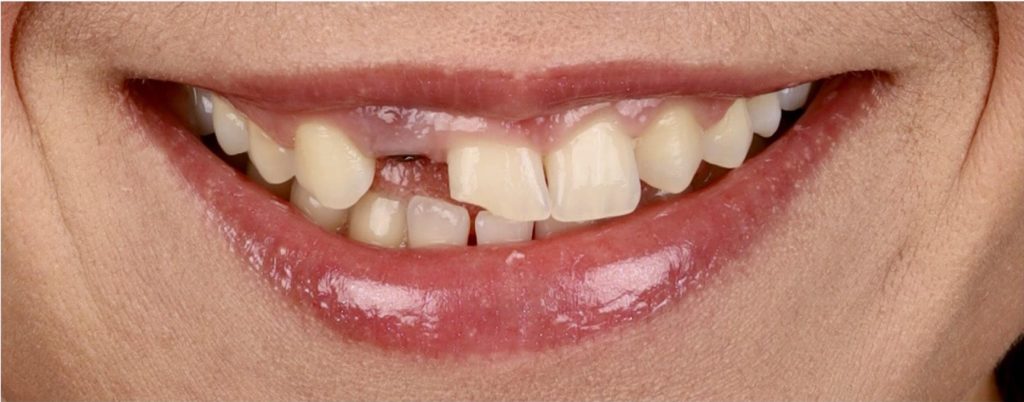

Aby osiągnąć taki efekt, musieliśmy przeprowadzić ekstrakcję złamanej górnej jedynki i w jej miejsce jednoczasowo wszczepić implant, a następnie na pozostałe zęby wykonać licówki i korony pełnoceramiczne w najjaśniejszym odcieniu.

Całość została zaprojektowana w harmonii z twarzą i rodzajem uśmiechu naszej Pacjentki. Leczenie trwało 3 miesiące.

Wykonał je lek.stom. Michał Badowski we współpracy z laboratorium Dentalscan (tech.dent. Joanna Gancarz).